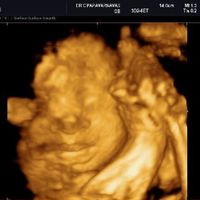

こんな感じで、初めての4Dエコーにとても感動して親バカが炸裂しました。 臨月になると、赤ちゃんにも脂肪がついてぎゅうぎゅうで入っているようで。 あの日見た美少女はどこへ? と戸惑いながらも冷静さを取り戻しました(笑) 実際生まれてきお子さんの可愛いエコー写真見せて下さい♡ 私のお気に入りのエコー写真です。 女の子です♡ 4Dエコーと同じ顔で産まれてくるのかどうか楽しみです٩ (ˊᗜˋ*) 2月22日 お気に入り 女の子 エコー写女の子は妊娠7ヶ月で判明が多い妊娠24週~26週のエコー写真 妊娠7ヶ月頃になると、多くの産院でエコー検査にて性別を調べてくれるようになります。 (産院の方針や妊婦の状況にもよる) この頃になると男の子のシンボルがエコーで見えない

なんだか急にお腹の赤ちゃんの存在がリアルになる 4dエコー写真